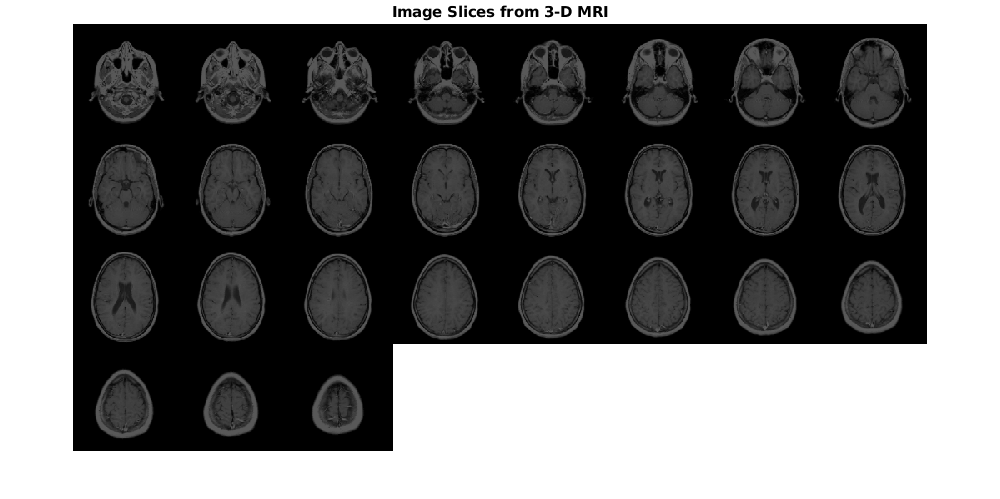

Отобразите фрагменты изображения от объема входа MRI как монтаж.

montage(mriVolume,'Size',[4 8],'BackgroundColor','w')

title('Image Slices from 3-D MRI','FontSize',14)